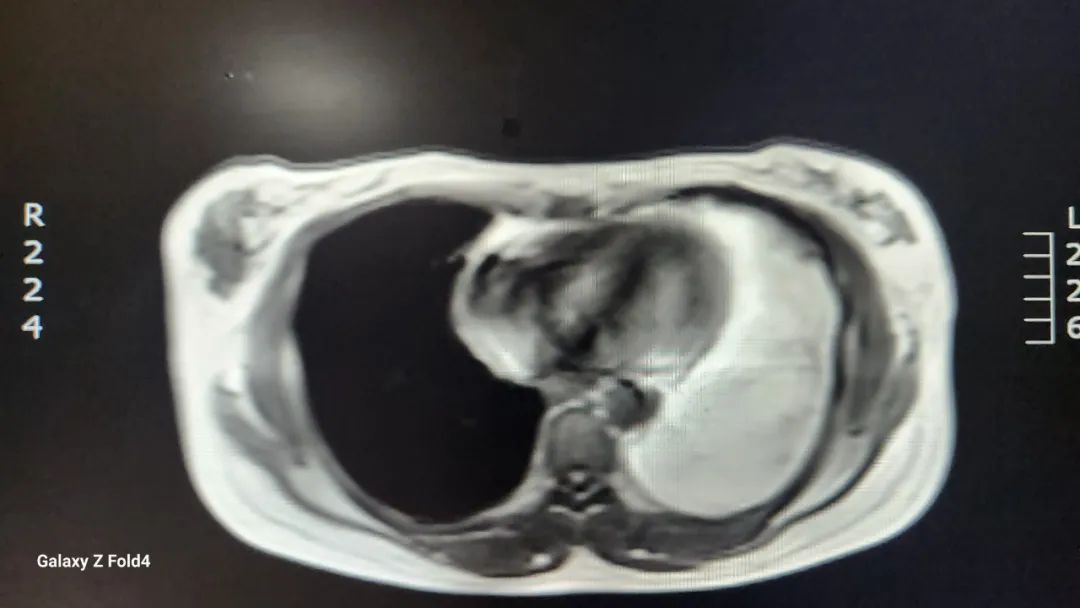

入住市中心医院胸外科后,胸CT检查示纵膈内心包左侧见团状脂肪密度影,较大层面大小约9.7*14.2厘米。完善纵隔磁共振等相关检查,根据检查结果高度怀疑纵膈内脂肪肉瘤。